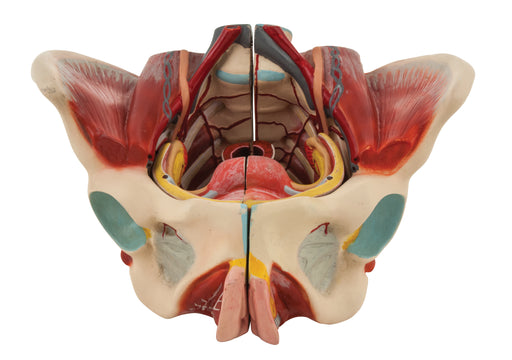

Female Muscle Pelvis - 4 Parts

Female Pevis Model separates into 4 parts because of median section and the removable inner organs.Representation of the external and internal geni...